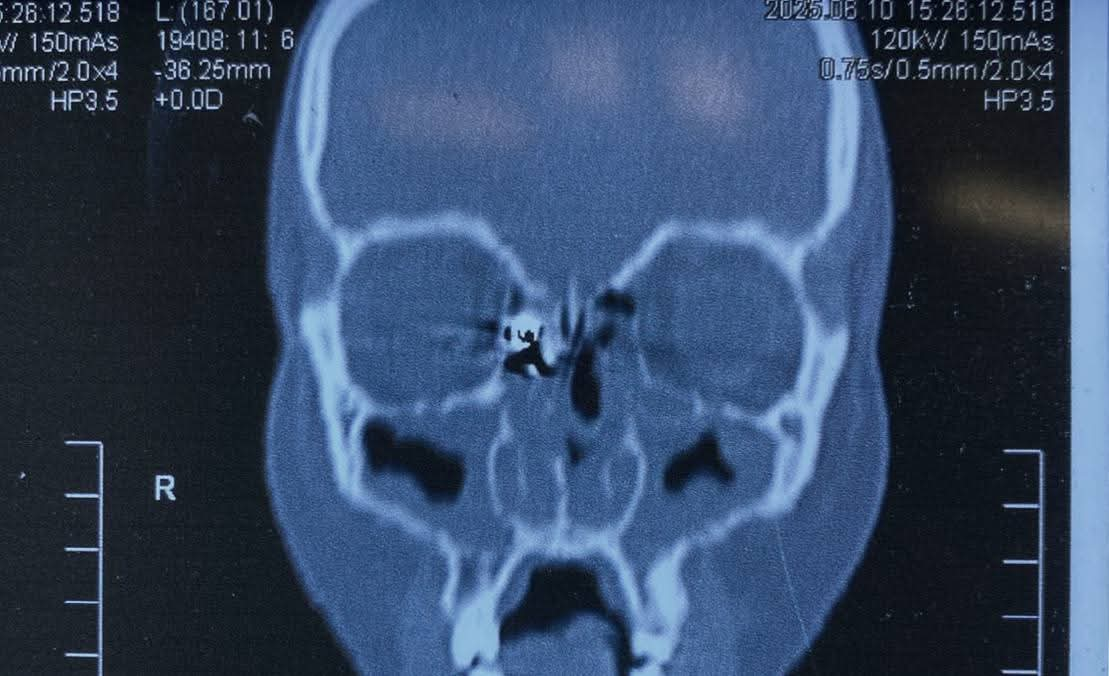

وكانت المريضة قد حضرت إلى المستشفى تعاني من نزيف بالأنف وتورم بالعين، عقب ادعائها الإصابة بطلق ناري من بندقية صيد، وعلى الفور، تم إجراء أشعة مقطعية على الأنف والجيوب الأنفية، والتي أظهرت وجود جسم غريب معدني مستقر داخل الجيوب الأنفية الغربالية.